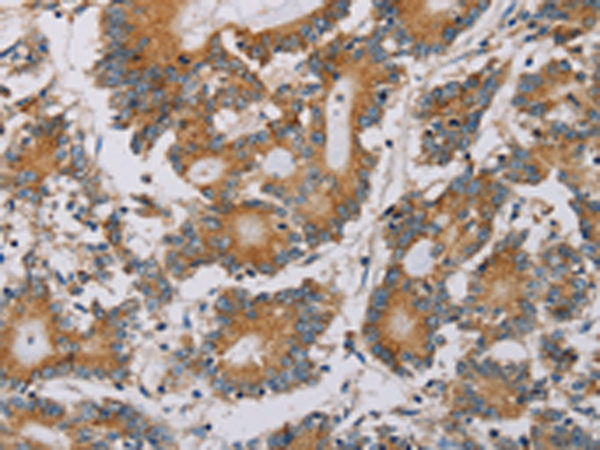

分类: 科研抗体货号: P08539别名: Bex; NADE; HGR74; NGFRAP1; DXS6984E应用: IHC反应种属: Human